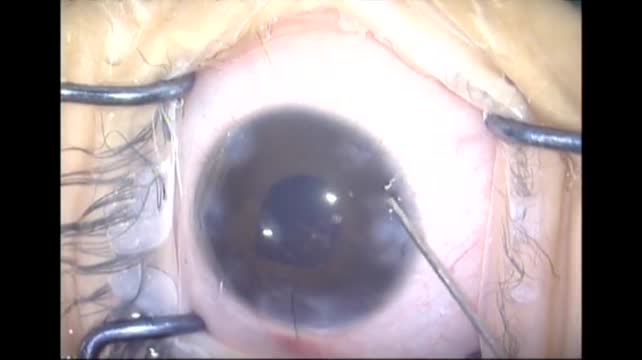

Nanophthalmos

Drs. O. Avedi, H. Smaoui, A. Jallouli, O. Hbaieb, and A. Trigui